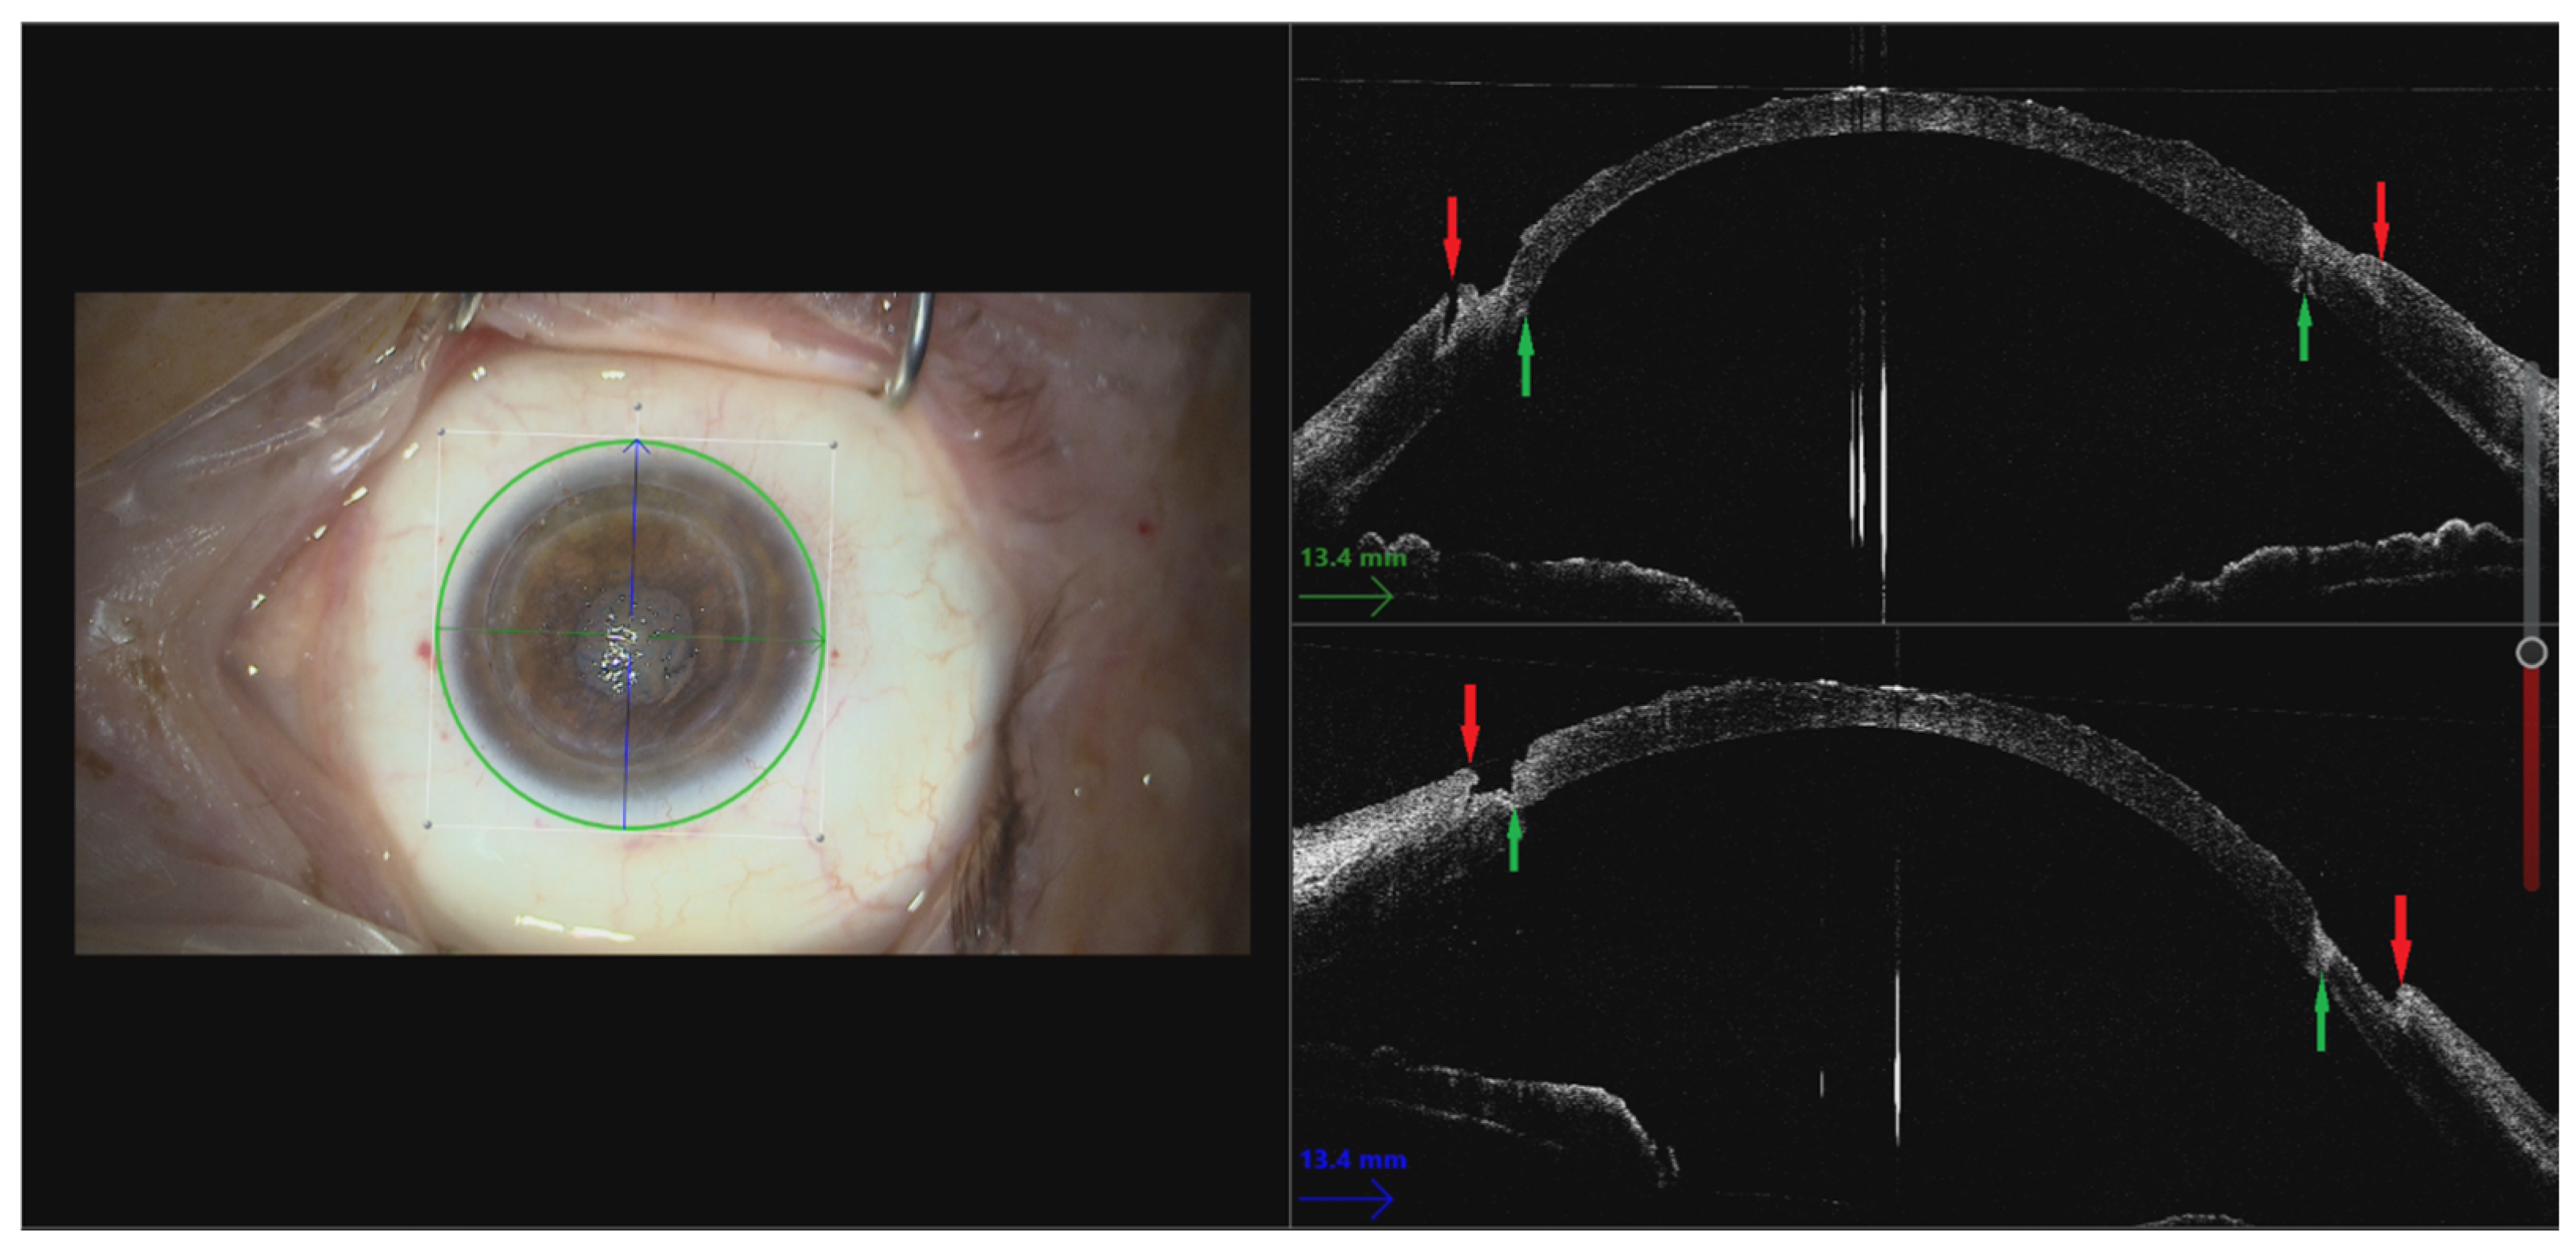

3.3. Recipient Bed Preparation

3.5. Use of Intraoperative OCT